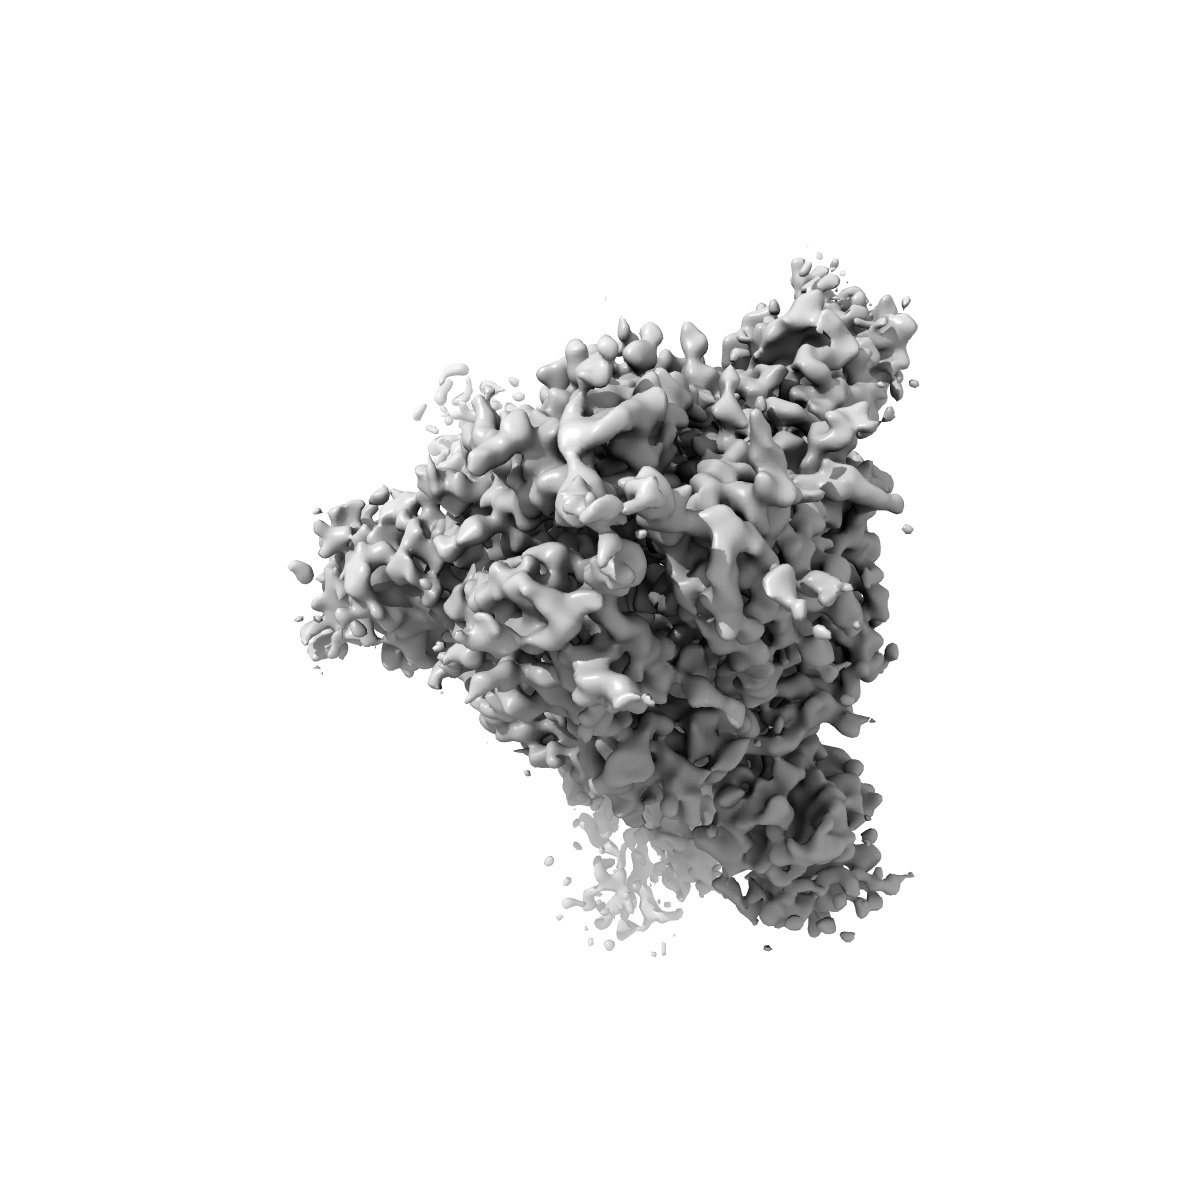

Structure of the SARS-CoV-2 S 6P trimer in complex with the human neutralizing antibody Fab fragment, BG1-24

Single-particle4.0 Å

Sample: Ternary complex of BG1-24 Fab bound to SARS-CoV-2 spike trimer